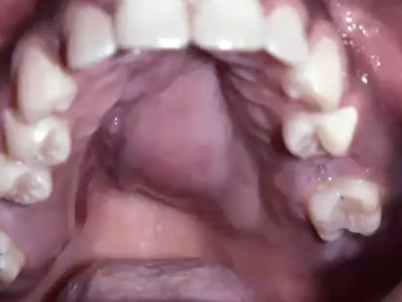

<p>What is the diagnosis?</p>

What is the diagnosis?

Nicotine stomatitis